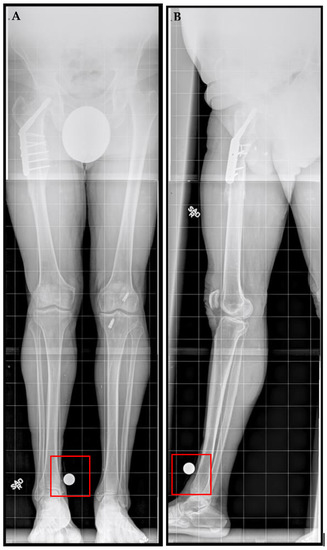

A right femoral osteoplasty was performed and a Precice MILN was inserted using the methods described above (Figure 2). The patient began lengthening as instructed on postoperative day five. He attended physical therapy and took vitamin D and calcium supplementation, as well as oxycodone as needed for pain management. Initial ROM of the knee joint was restricted from 0–50°, but full range was regained two months after surgery. He finished distraction 46 days after surgery (Figure 3). The patient completed consolidation 152 days after surgery and experienced no complications. At his latest follow-up appointment, his long leg films (Figure 4) demonstrated complete healing, remodeling, and equal limb length. The patient has returned to his active lifestyle, including skiing, and reported that he felt better on his bike and skis.

Figure 4.

Post-traumatic femoral lengthening in a 71-year-old male patient at his final follow-up appointment. (A) Anteroposterior bilateral long leg and (B) lateral right long leg after consolidation of regenerate, with Precice MILN in place. Gray dots on the bottom represent X-ray calibration spheres.